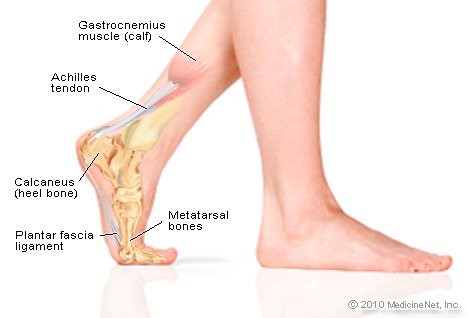

Can Plantar Fasciitis Cause Calf Pain Sidekick Blog new arrivals, My calves and feet hurt do I have plantar fasciitis Kelly new arrivals, Are You Sure It s Plantar Fasciitis Think Again. Rehab Renegade new arrivals, Trigger Points and Plantar Fasciitis Body Heal Therapy new arrivals, Relief plantar fasciitis pain in calf by stretching and proper support new arrivals, Plantar Fasciitis Treatment Oakville Shockwave Therapy new arrivals, Plantar Fasciitis Symptoms Causes Treatment Options new arrivals, Part One Stretching For Plantar Fasciitis new arrivals, Plantar fasciitis treatment symptoms and causes healthdirect new arrivals, Plantar Fasciitis Treatment Calf Stretches new arrivals, ProStretch The Original Calf Stretcher and Foot Rocker for Plantar new arrivals, Treating Plantar Fasciitis with RockTape RockPods RockTape new arrivals, Plantar fasciitis can be a very NeuroKinetic Therapy Facebook new arrivals, plantar fasciitis new arrivals, Plantar Fasciitis Exercises to Cure Heel Pain sFera Fitness new arrivals, Are You Sure It s Plantar Fasciitis Think Again. Rehab Renegade new arrivals, Tight Calves and Plantar Fasciitis Understanding the Link new arrivals, Calf Stretches For Plantar Fasciitis Achilles Tendonitis Right new arrivals, Calf.Bar Treat heel pain at the source Calf.bar Facebook new arrivals, Plantar Fasciitis Causes Symptoms Treatments and More new arrivals, Feet First Newry Foot Clinic Tight Calf muscles new arrivals, Plantar Fasciitis Arvada Sport Spine new arrivals, Stretches for Plantar Fasciitis You Need to Know for Pain Relief new arrivals, My calves and feet hurt do I have plantar fasciitis Kelly new arrivals, Plantar fasciitis Wikipedia new arrivals, Pain In The Back Of The Heel May Mean You Have Other Problems new arrivals, ProStretch Plus Customizable and Adjustable Calf Stretcher and Foot Rocker for Plantar Fasciitis Achilles Tendonitis and Tight Calves Made in USA new arrivals, Treating Plantar Fasciitis With Calf Stretches james new arrivals, How to treat plantar fasciitis new arrivals, 3 of the Most Common Risk Factors for Plantar Fasciitis John A new arrivals, 5 Ways To Treat Plantar Fasciitis Pain Road Runner Sports Road new arrivals, Plantar Fasciitis 10 Tools for Successful Patient Pain Relief new arrivals, This Stretch Helps Relieve Plantar Fasciitis and Heel Pain Live new arrivals, What s a Plantar Fasciitis EVA Orthotic Insoles Manufacturer new arrivals, Plantar fasciitis stretches 6 exercises for heel pain relief new arrivals, How to Heal Heel Pain from Plantar Fasciitis Foot Dynamics new arrivals, Best Calf Stretches For Plantar Fasciitis new arrivals, Treatments for Heel Pain Ottawa Foot Clinic new arrivals, Plantar Fasciitis ChiroKinetix Sports Medicine Clinic new arrivals, Trigger Points and Plantar Fasciitis Body Heal Therapy new arrivals, Acupuncture for Calf Trigger Points Morningside Acupuncture NYC new arrivals, Plantar Fasciitis Therapy Superior Physical Therapy new arrivals, Exercises to help prevent plantar fasciitis Mayo Clinic new arrivals, 5 Steps to Decreasing the Pain and Discomfort of Plantar Fasciitis new arrivals, Plantar Fasciitis What Is It Symptoms Treatment and More Osmosis new arrivals, Plantar Fasciitis Exercises new arrivals, Treating heel pain and plantar fasciitis at home Performance new arrivals, Plantar Fasciitis and Bone Spurs OrthoInfo AAOS new arrivals, Evaluation of Plantar Fasciitis Treatments Sydney Heel Pain Clinic new arrivals, Pin on My Style new arrivals.

Plantar fasciitis calf pain new arrivals